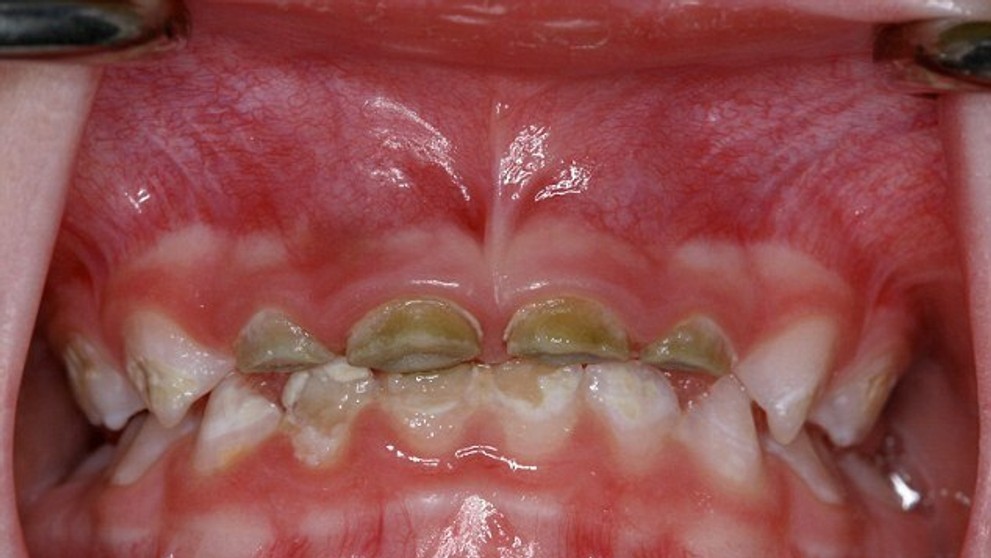

Znepokojujúce fotky detských zubov. Toto spôsobujú sladené nápoje

Vek, kedy sa deťom začínajú kaziť zuby sa stále znižuje. To, že dentisti plombujú mliečne zuby, už nie je žiadna rarita. Keď ale 18-mesačné dieťa príde o celý mliečny chrup, to už je viac než alarmujúce. Rodičia podceňujú výber nápojov, ktorý deťom ponúkajú. Aj keď majú ratolesti najradšej sladké džúsy a malinovky, mamičky by ich chúťky mali ignorovať. Ak ste vy tak doteraz neurobili, pozrite sa, čo všetko spôsobujú sladené nápoje.

Ak ratolesti, ktoré obľubujú sladené nápoje, nemajú ani vzťah k umývaniu si zubov, potom je to čistá pohroma a so zdravým mliečnym chrupom sa môžu rozlúčiť. Zubár odporúča rodičom, aby deťom obmedzili príjem cukru najmä medzi hlavnými jedlami.

Denník DailyMail zverejnil šokujúce snímky malých detí, ktoré si zničili chrup skôr, než im poriadne narástol. Fotky im poskytli austrálski dentisti, ktorí tak nad nedôslednými rodičmi zdvíhajú varovný prst.